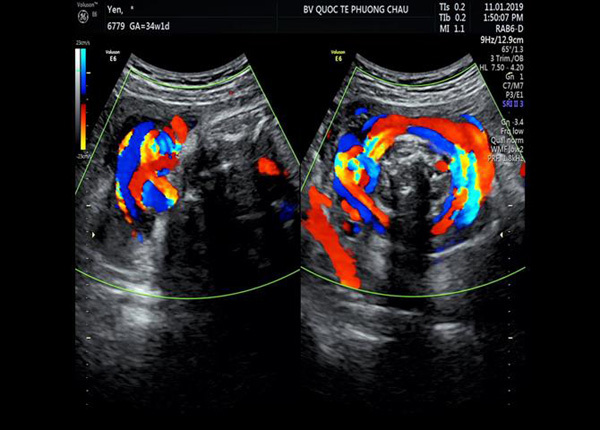

23h cùng ngày, sau đánh giá lại, bé tỉnh, môi hồng/NCPAP kèm chi ấm, mạch rõ, thở đều, SPO2 99%, phổi thông khí đều, tim đều, bụng mềm, phản xạ khá. Đến hôm nay, chiến binh bé bỏng đã dũng cảm vượt qua, cai thở NCPAP, chuyển qua thở oxy cannula mũi 0.5 l/ph.

Chính kết luận siêu âm phát hiện kịp thời từ kỹ thuật hiện đại, hỗ trợ cho kinh nghiệmcủa BS Sản khoa Phương Châu trong chẩn đoán đã đánh đổi xứng đáng bằng giá trị an toàn và tính kịp thời bảo vệ tính mạng thai nhi trong xử lý trường hợp này.